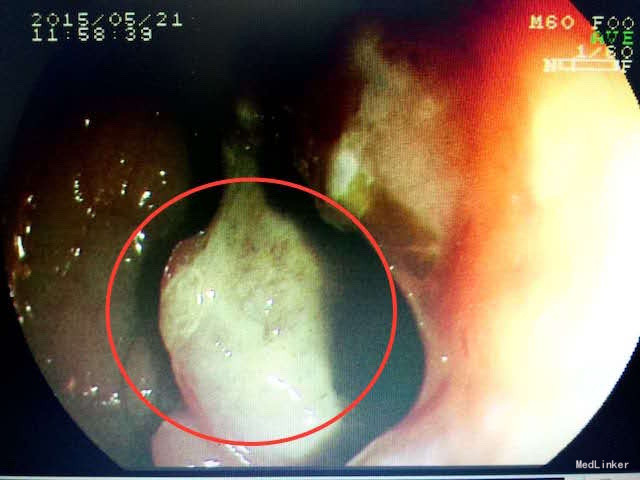

肠镜及活检结果:升结肠中-低分化腺癌。 治疗:腹腔镜右半结肠癌切除术,术后化疗。